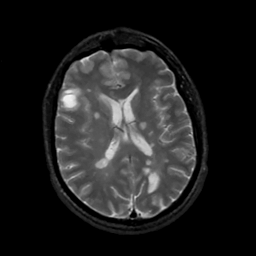

MR Study #5, March 10, 1991 -- Slice #31